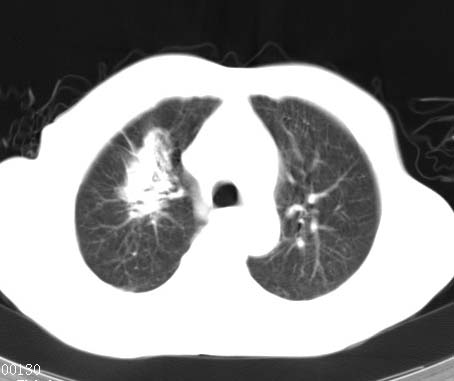

右上肺结核,请结合痰检除外活动期;右上叶支气管官腔狭窄建议支气管镜或抗僗后随诊除外堵塞性改变。

高度怀疑肺癌,强烈要求纤支镜检查。

支持双上肺继发性肺结核。